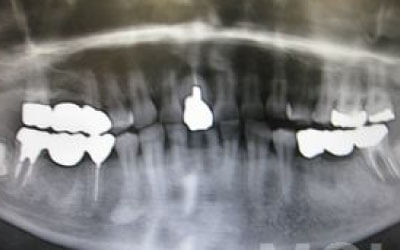

CTを使うことで、骨や歯の状態を3Dで確認でき、正確な距離測定も行えます。

骨の厚さや傾き、神経の位置などを事前にしっかりと計測することで、安全にインプラント治療を行うことができます。

しかし、事前にCTを撮影し、三次元的に神経までの距離を計測して治療計画を立てれば、心配することはありません。

また、過剰に削らないようにストッパーも使用しているため、安全に治療が進められます。